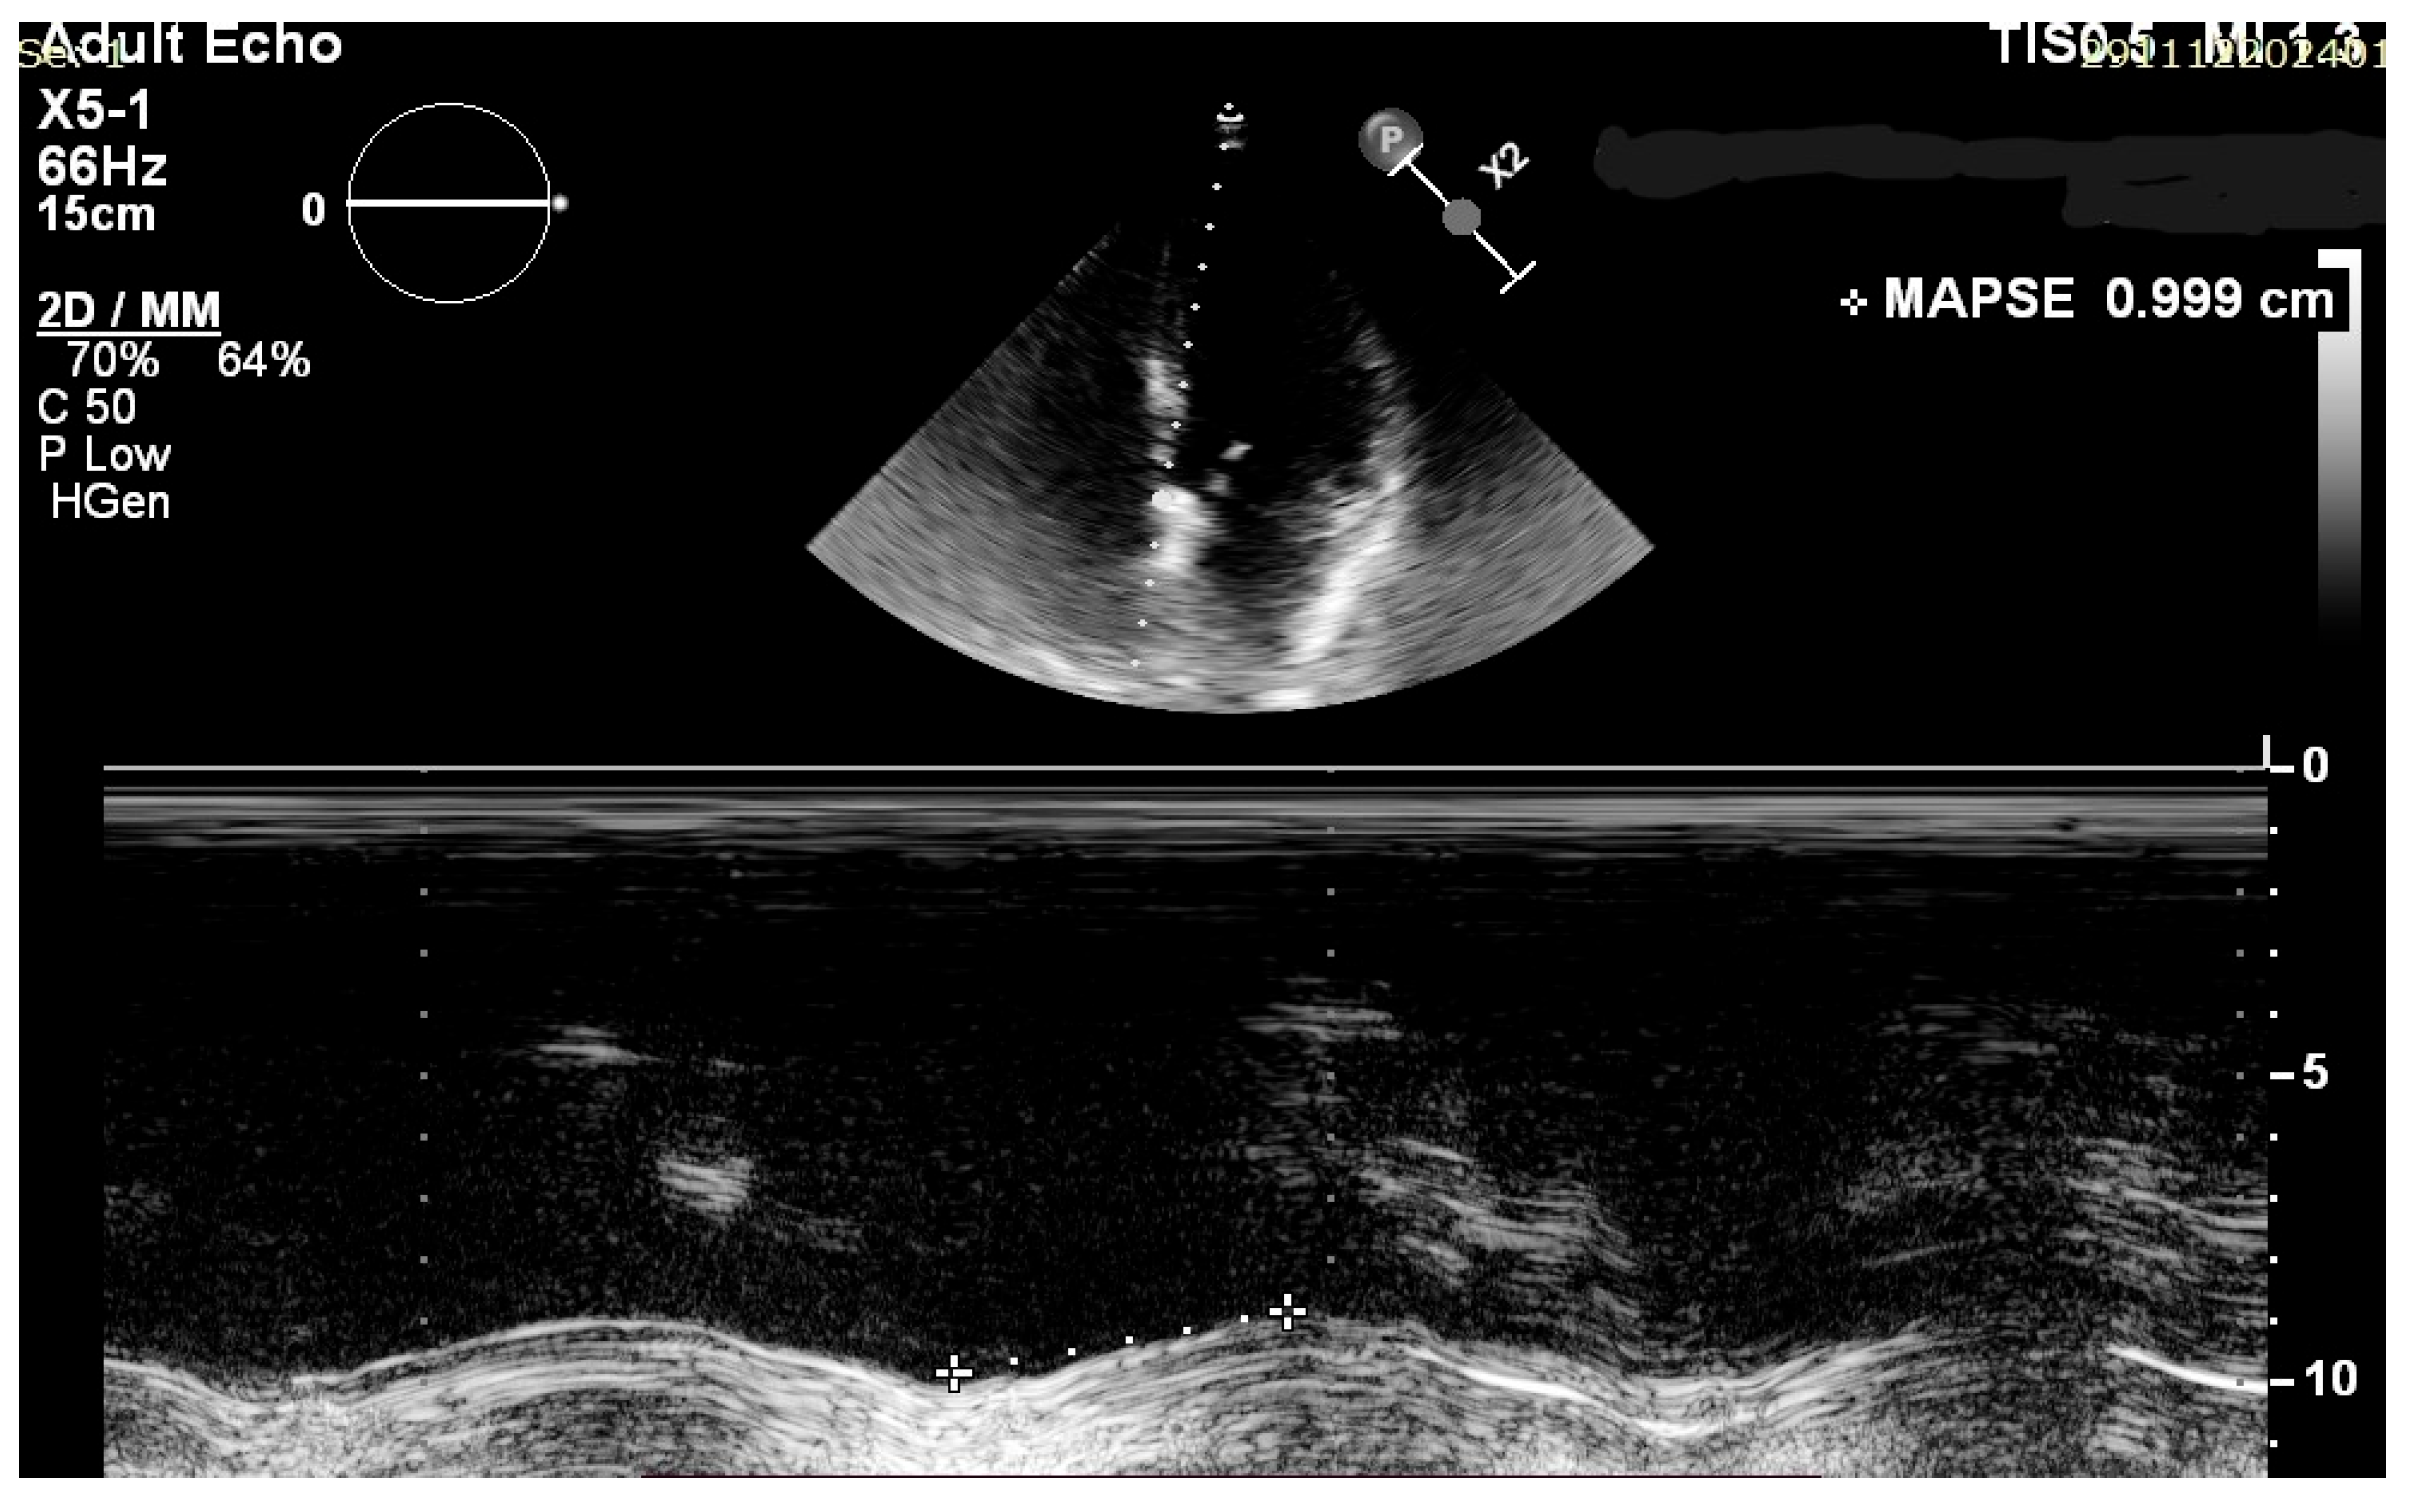

2.3. Echocardiographic Assessment

| Avg MAPSE (mm) | 13.65 | 2.05 |

| Septal MAPSE (mm) | 13.15 | 2.02 |

| Lateral MAPSE (mm) | 14.16 | 1.97 |

| Average MAPSE | 0.89 | <0.001 |

| Septal MAPSE | 0.90 | |

| Lateral MAPSE | 0.88 |